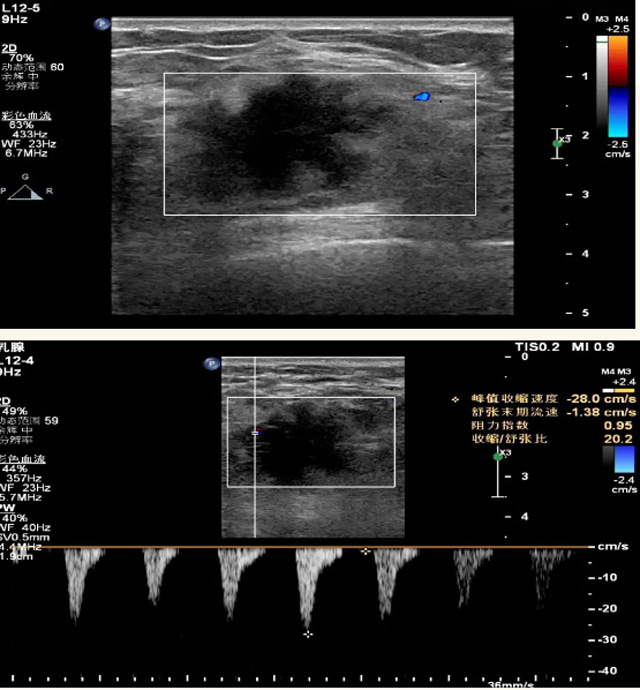

乳腺B超檢查無(wú)輻射,對(duì)囊性病變敏感,可以實(shí)時(shí)觀察病灶。超聲引導(dǎo)活檢跟手術(shù)前的定位。就是它對(duì)于微小的鈣化查出率比鉬靶稍微差點(diǎn)。磁共振MRI檢查也是是沒有輻射的,對(duì)備孕跟已經(jīng)懷孕的人士比較友好。不用擔(dān)心這個(gè)輻射影響胎兒?jiǎn)栴}。對(duì)乳腺病灶敏感性較高,致密乳腺病灶、乳腺癌的復(fù)發(fā),準(zhǔn)確鑒別囊性及實(shí)性病變??梢詭椭R床醫(yī)生判斷惡性、良性病變。但是MRI磁共振對(duì)微小鈣化不明顯,微鈣化還是鉬靶靠譜點(diǎn)。檢查時(shí)間比較長(zhǎng),有偽影的影響。費(fèi)用相對(duì)B超,鉬靶高很多。

乳腺B超

磁共振MRI